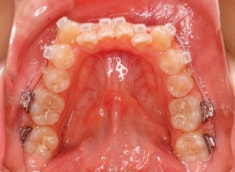

治療前

治療開始時